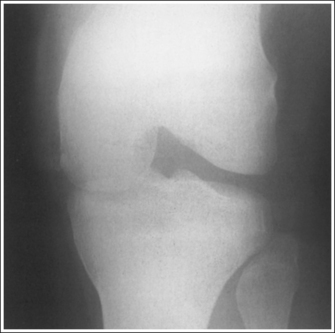

• Patellar subluxation. With patellar subluxation (partial patellar dislocation), the patella may be situated more laterally than normal on an AP knee projection (see Image 61). When an image demonstrates a laterally situated patella, evaluate the symmetry of the femoral condyles and the relationship of the tibia and fibular head to rule out external rotation before assuming that the patella is subluxed. External rotation also results in a laterally located patella.

IMAGE 61

The lateral knee compartment is narrower than the medial knee compartment. The patient's knee demonstrates a valgus deformity.

The medial knee compartment is narrower than the lateral knee compartment. The patient's knee demonstrates a varus deformity.